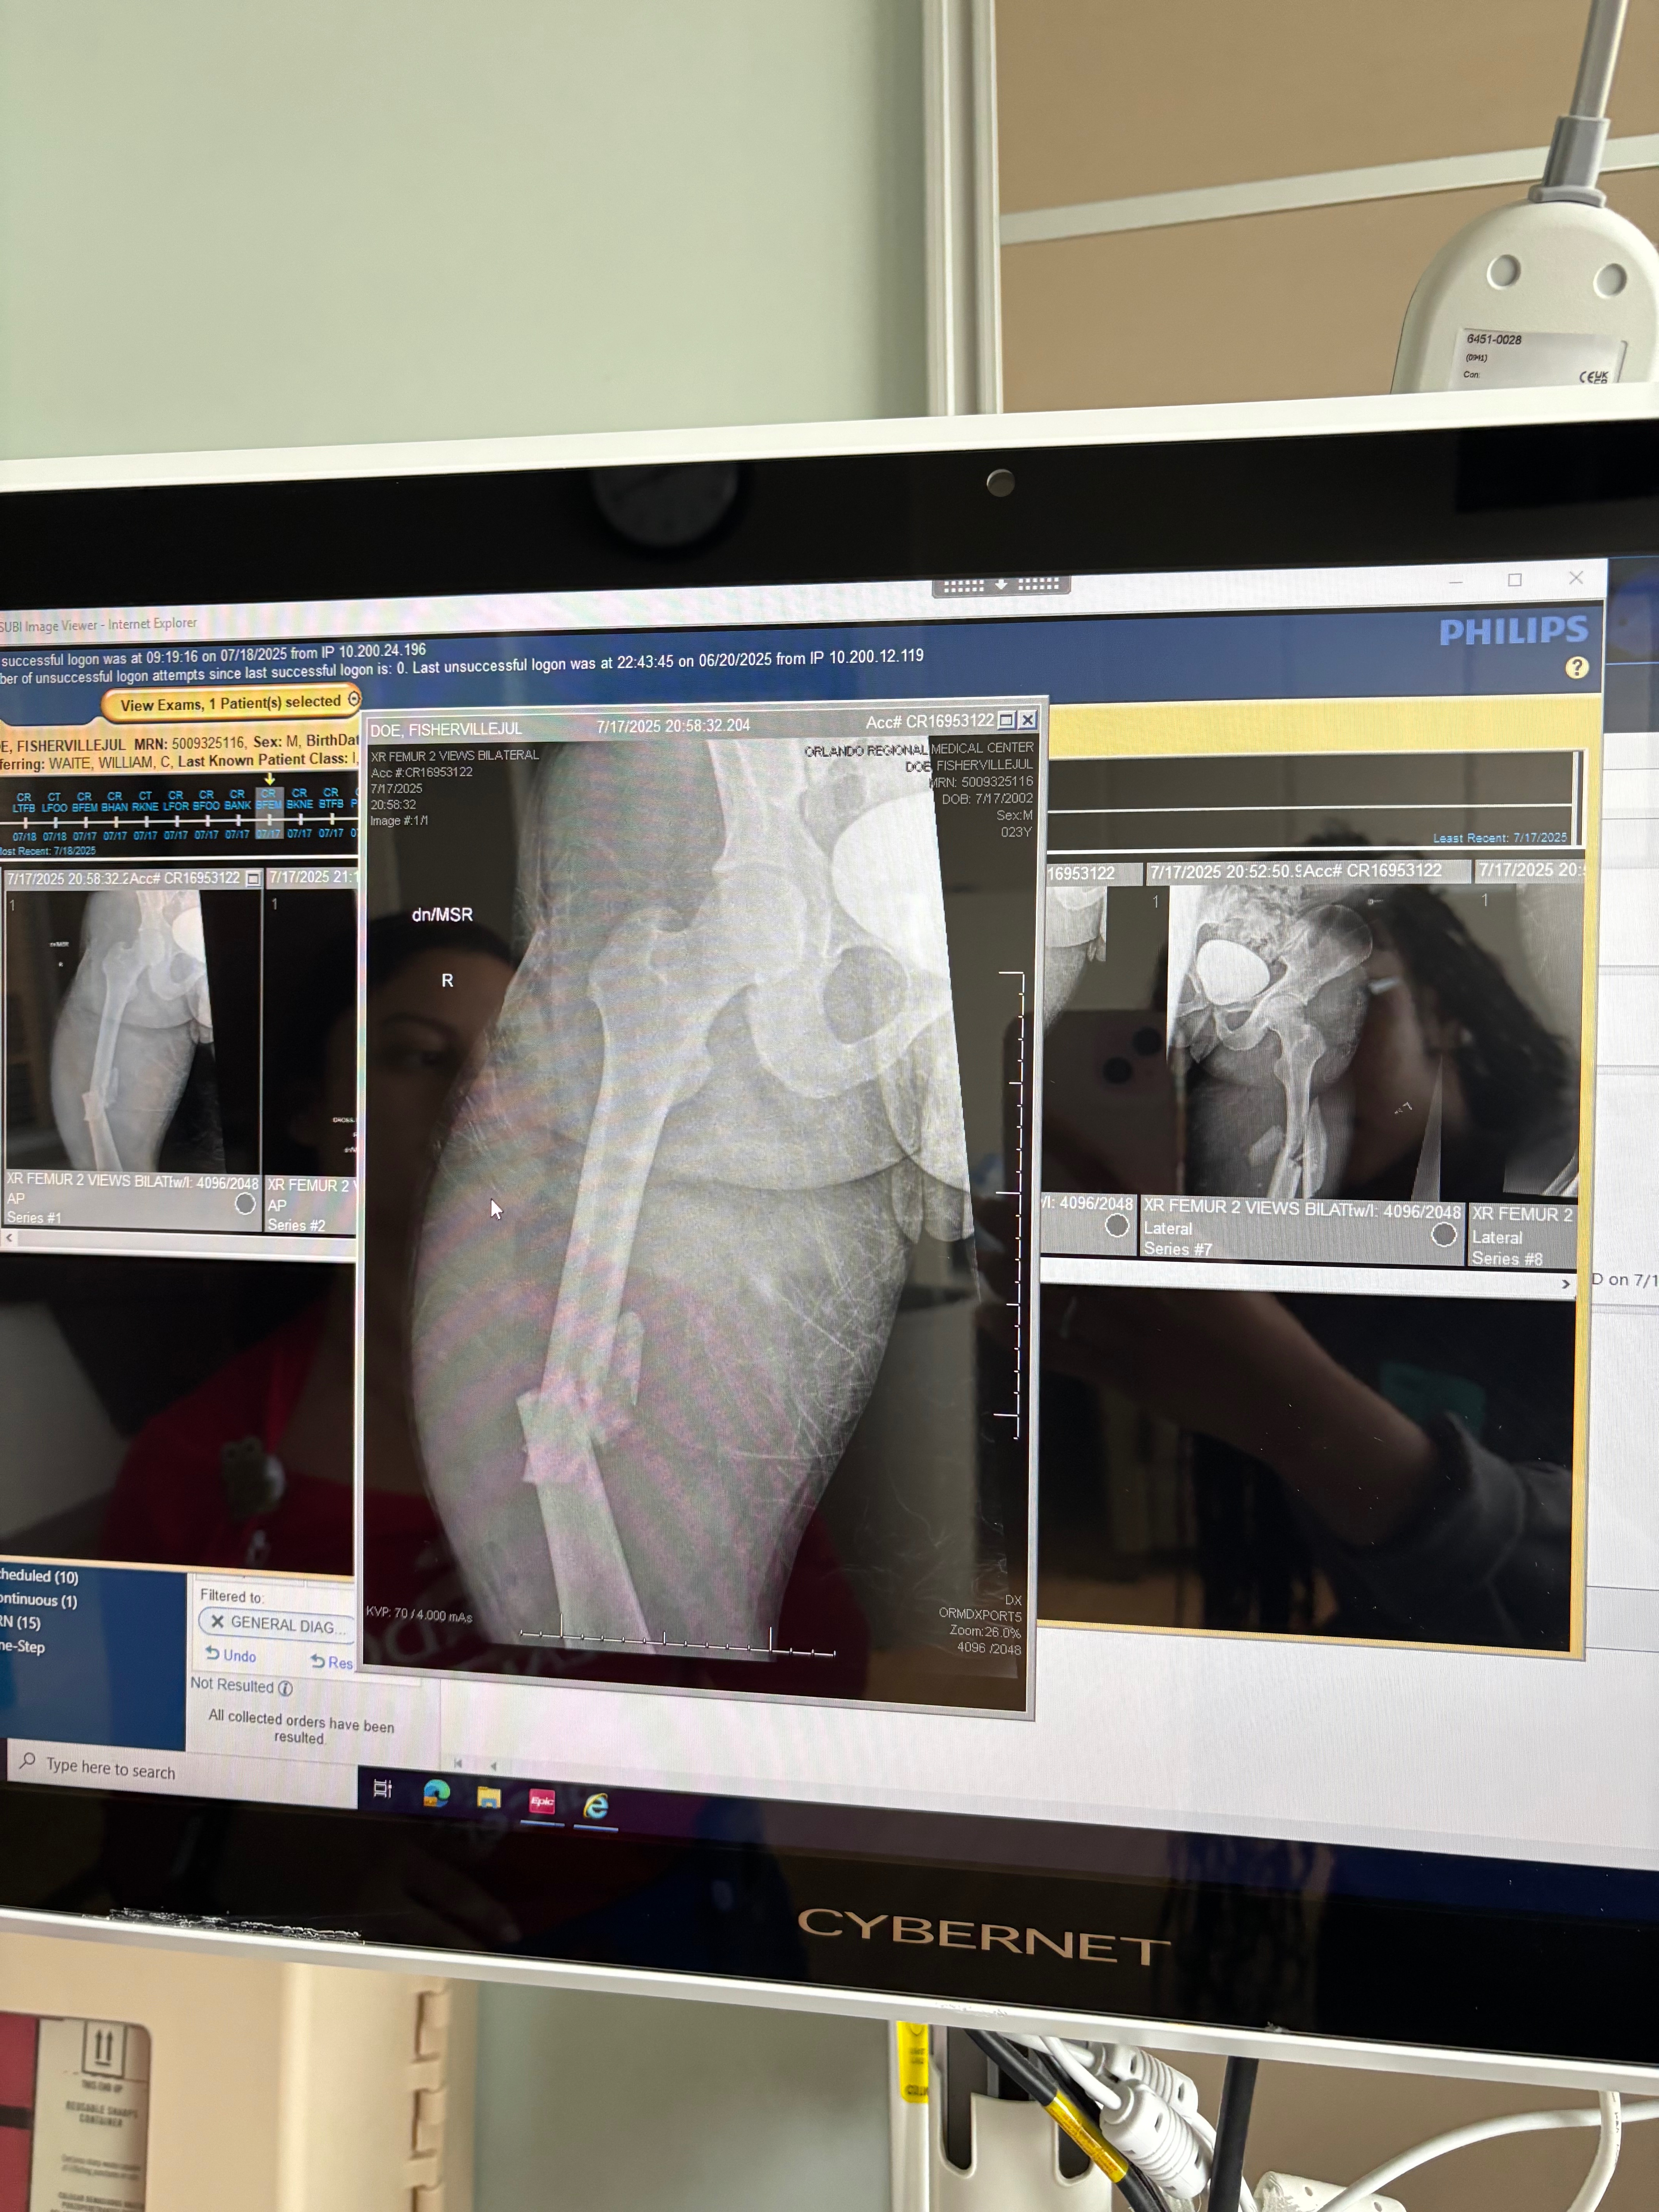

I was rushed to the hospital, in an ambulance and they immediately began working on me. The doctors told me both of my femurs and my shin were shattered and that I have multiple other injuries, and this is just the beginning. I’ll need more surgeries, months of physical therapy, and help doing even the most basic things.